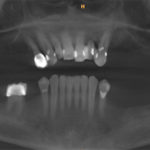

All on 4 Case 1

Before

Male

Dr. Cavaretta